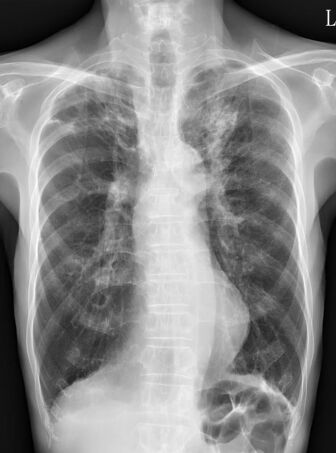

21. 黃先生68歲,有慢性阻塞性肺病(chronic obstructive pulmonary disease, COPD)的病史。因為發燒三天,合併呼吸急促與咳嗽有黃濃痰的狀況來到急診。黃先生自訴三個月前曾經因為慢性阻塞性肺病急性發 作(COPD exacerbation)住院一週,使用過類固醇與注射型抗生素。於急診時理學檢查發現呼吸急促,意識清楚。體溫 38.6°C, 心跳110 /minute, 血壓 136/80 mm Hg, 呼吸速率 26 /minute, 不使用氧氣的情況下SPO2: 91%,CXR如圖所示。WBC: 12,000 /mm³, platelet count: 159,000 per /mm³, BUN 26 mg /dl, creatinine 1.2 mg/dl。於急診的處置下列何者不適當?

(A) 進行SARS-CoV-2以及influenza的檢測。 (B) 進行痰液與血液的細菌培養。 (C) 給予口服抗生素治療即可返家。 (D) 給予Beta-lactam + Macrolide的抗生素治療。 (E) 可考慮給予針對Pseudomonas aeruginosa的抗生素治療。